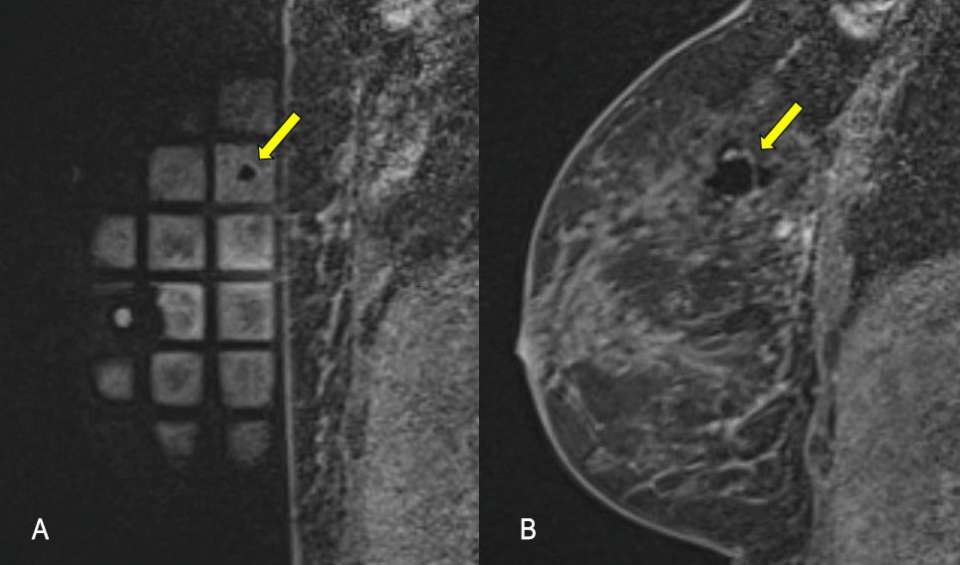

Figure 3A and 3B. Sagittal T1-weighted fat saturated post contrast images demonstrate the biopsy tract and post sampling changes.

- Confirm biopsy of the target site with a post-biopsy scan (fig 3a and 3b)